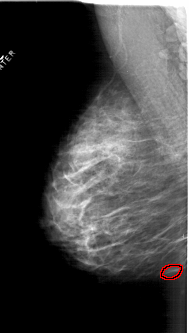

A_1814_1.LEFT_MLO

LEFT_MLO LINES 6316 PIXELS_PER_LINE 3586 BITS_PER_PIXEL 12 RESOLUTION 43.5 OVERLAY

FILE: A_1814_1.LEFT_MLO.OVERLAY

TOTAL_ABNORMALITIES 1

ABNORMALITY 1

LESION_TYPE MASS SHAPE OVAL MARGINS CIRCUMSCRIBED

ASSESSMENT 3

SUBTLETY 3

PATHOLOGY BENIGN

TOTAL_OUTLINES 1

BOUNDARY